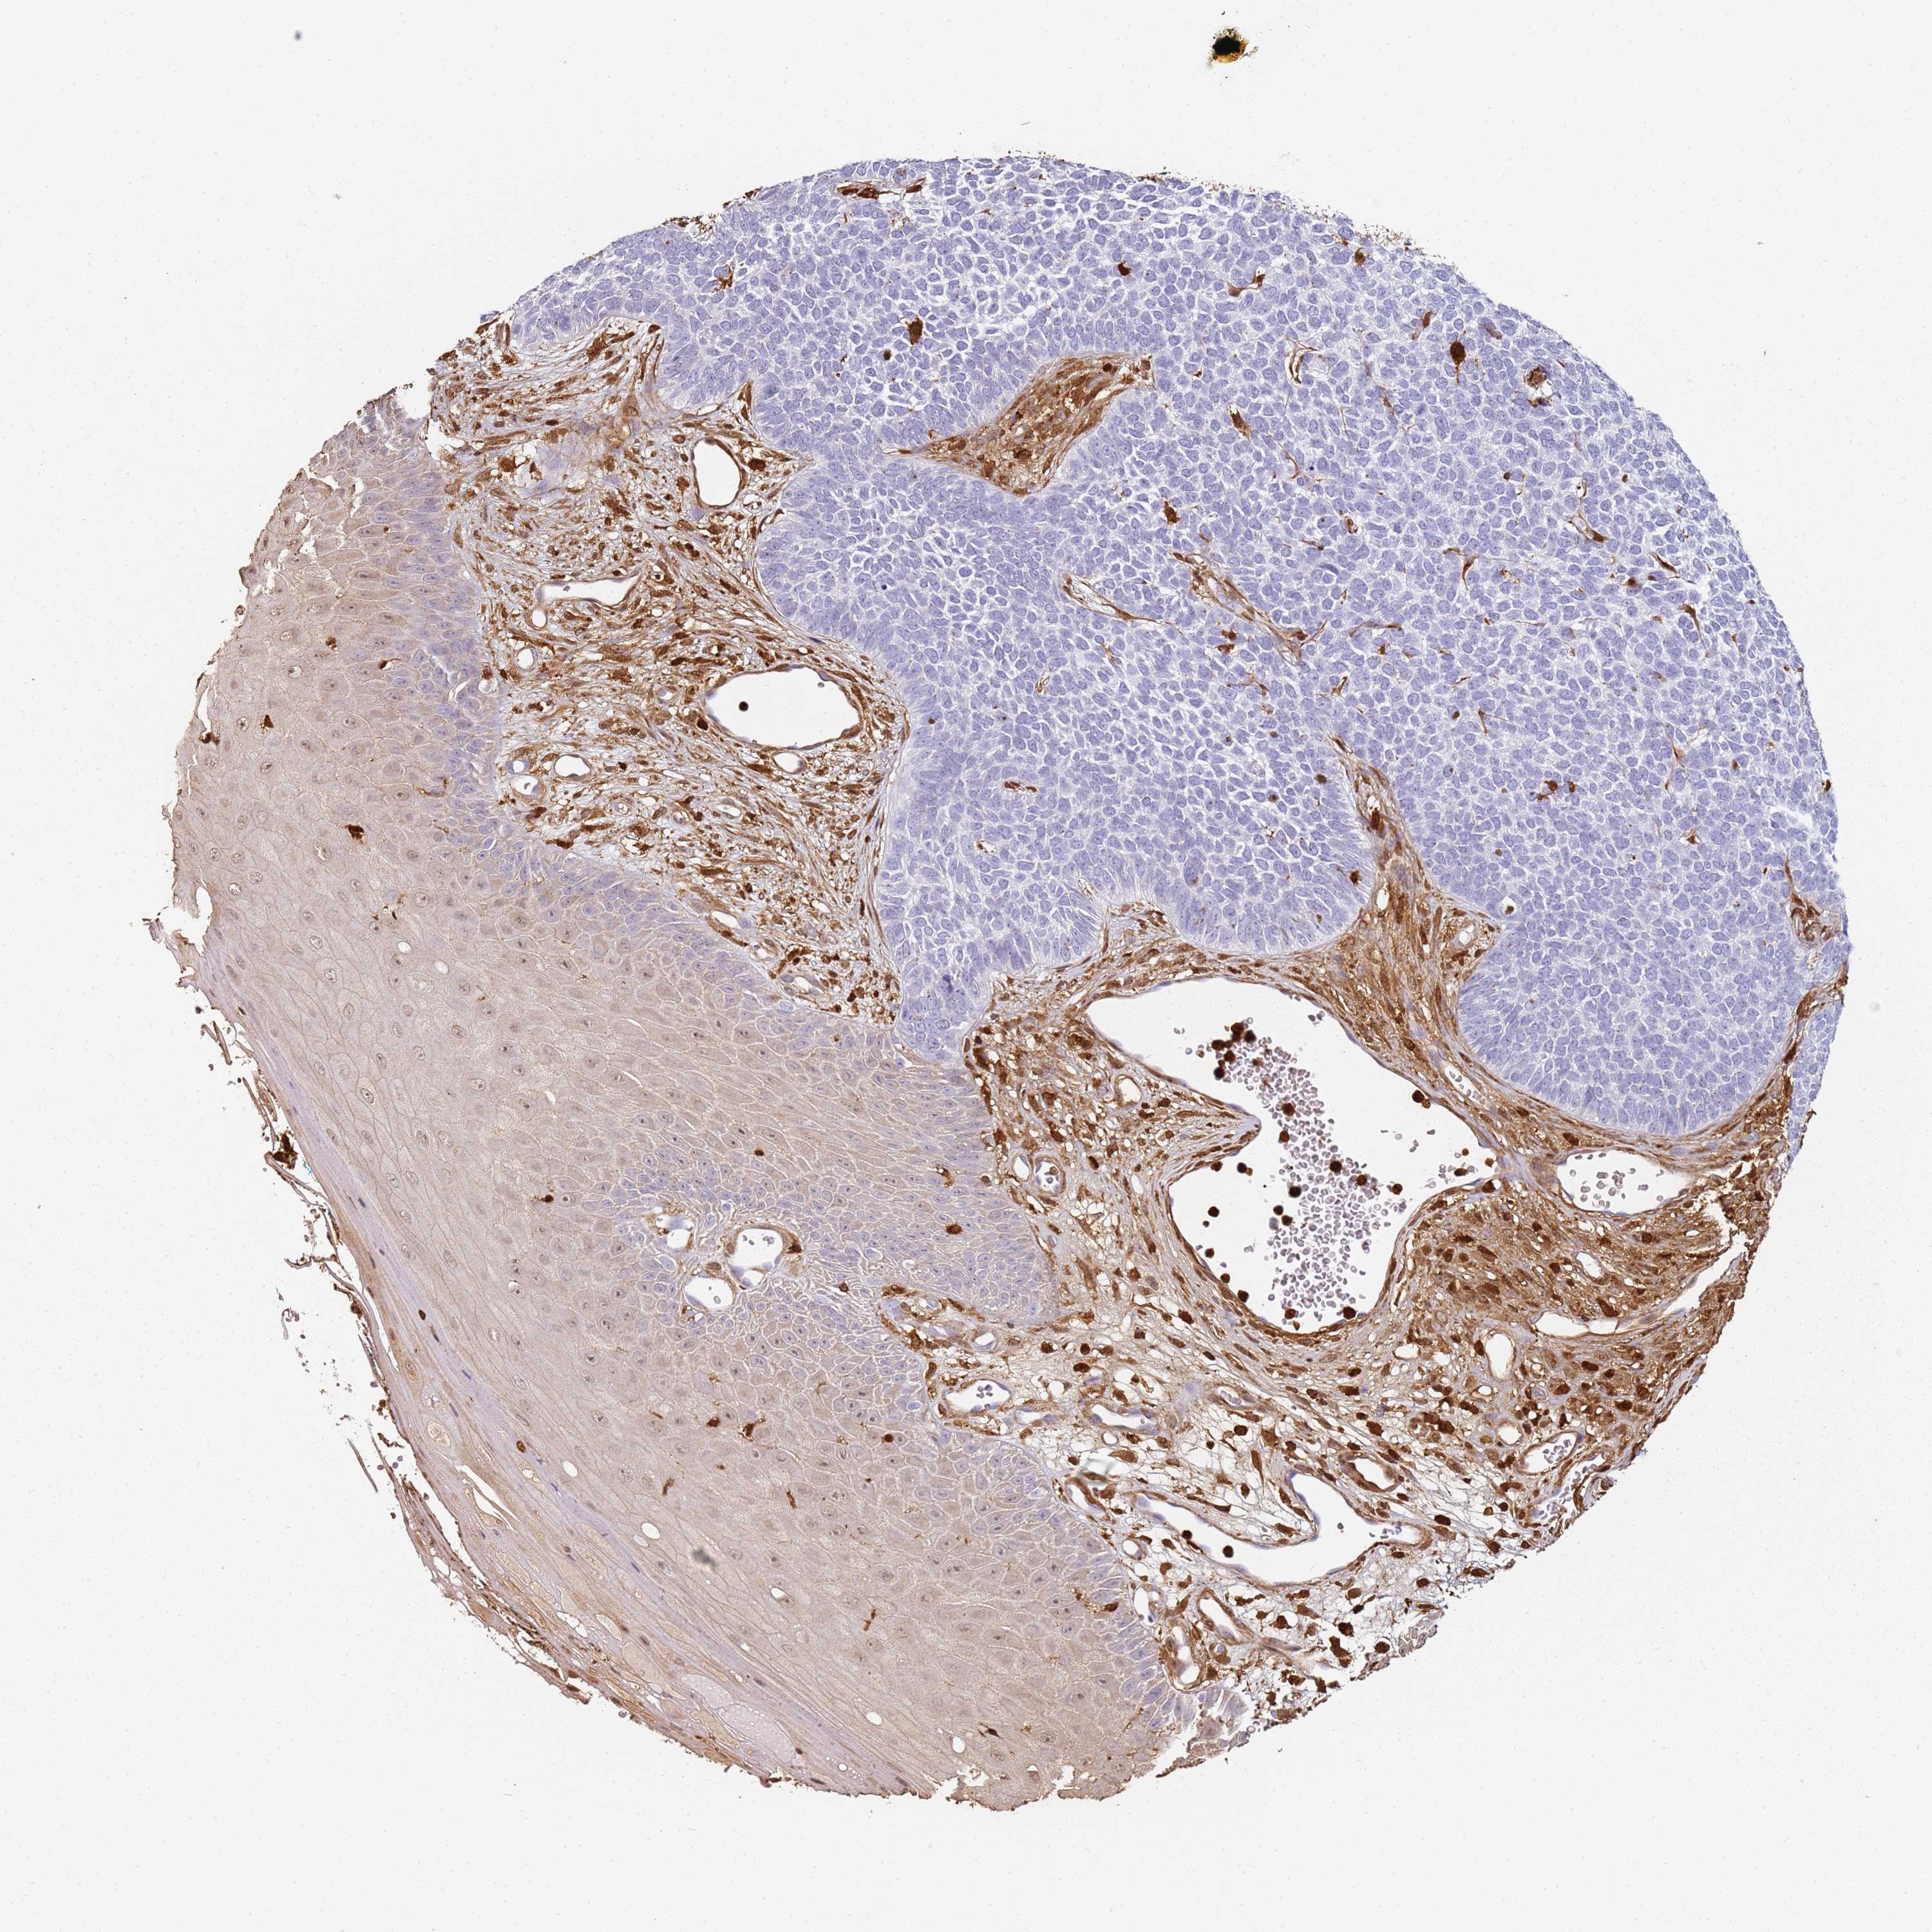

CANCER SKIN CANCER Show tissue menu

Basal cell and squamous cell cancer

SKIN CANCER - Protein expressioni

A mouse-over function shows sample information and annotation data. Click on an image to view it in a full screen mode. Samples can be filtered based on level of antibody staining by selecting one or several of the following categories: high, medium, low and not detected. The assay and annotation is described here.

Each image is clickable and will lead to virtual microscopy that enables deeper exploration of all samples and also displays staining intensity scores, fraction scores and subcellular localization as well as patient and tissue information for each sample.

CAB027387

Squamous cell carcinoma, metastatic, NOS